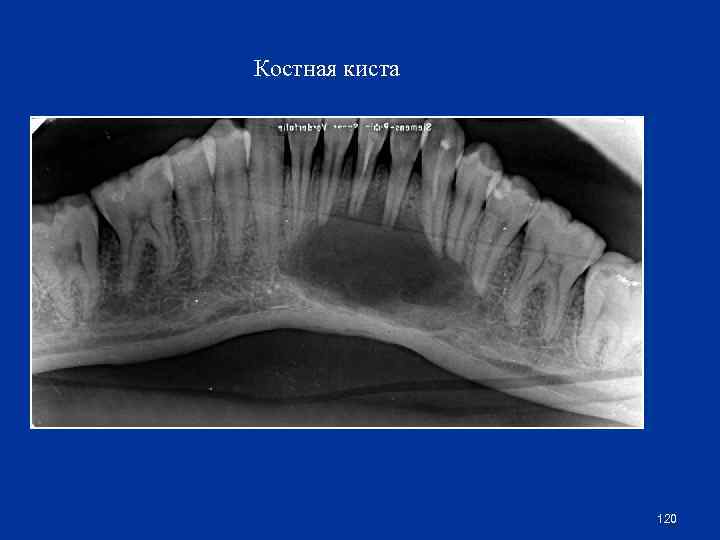

Костная киста 120